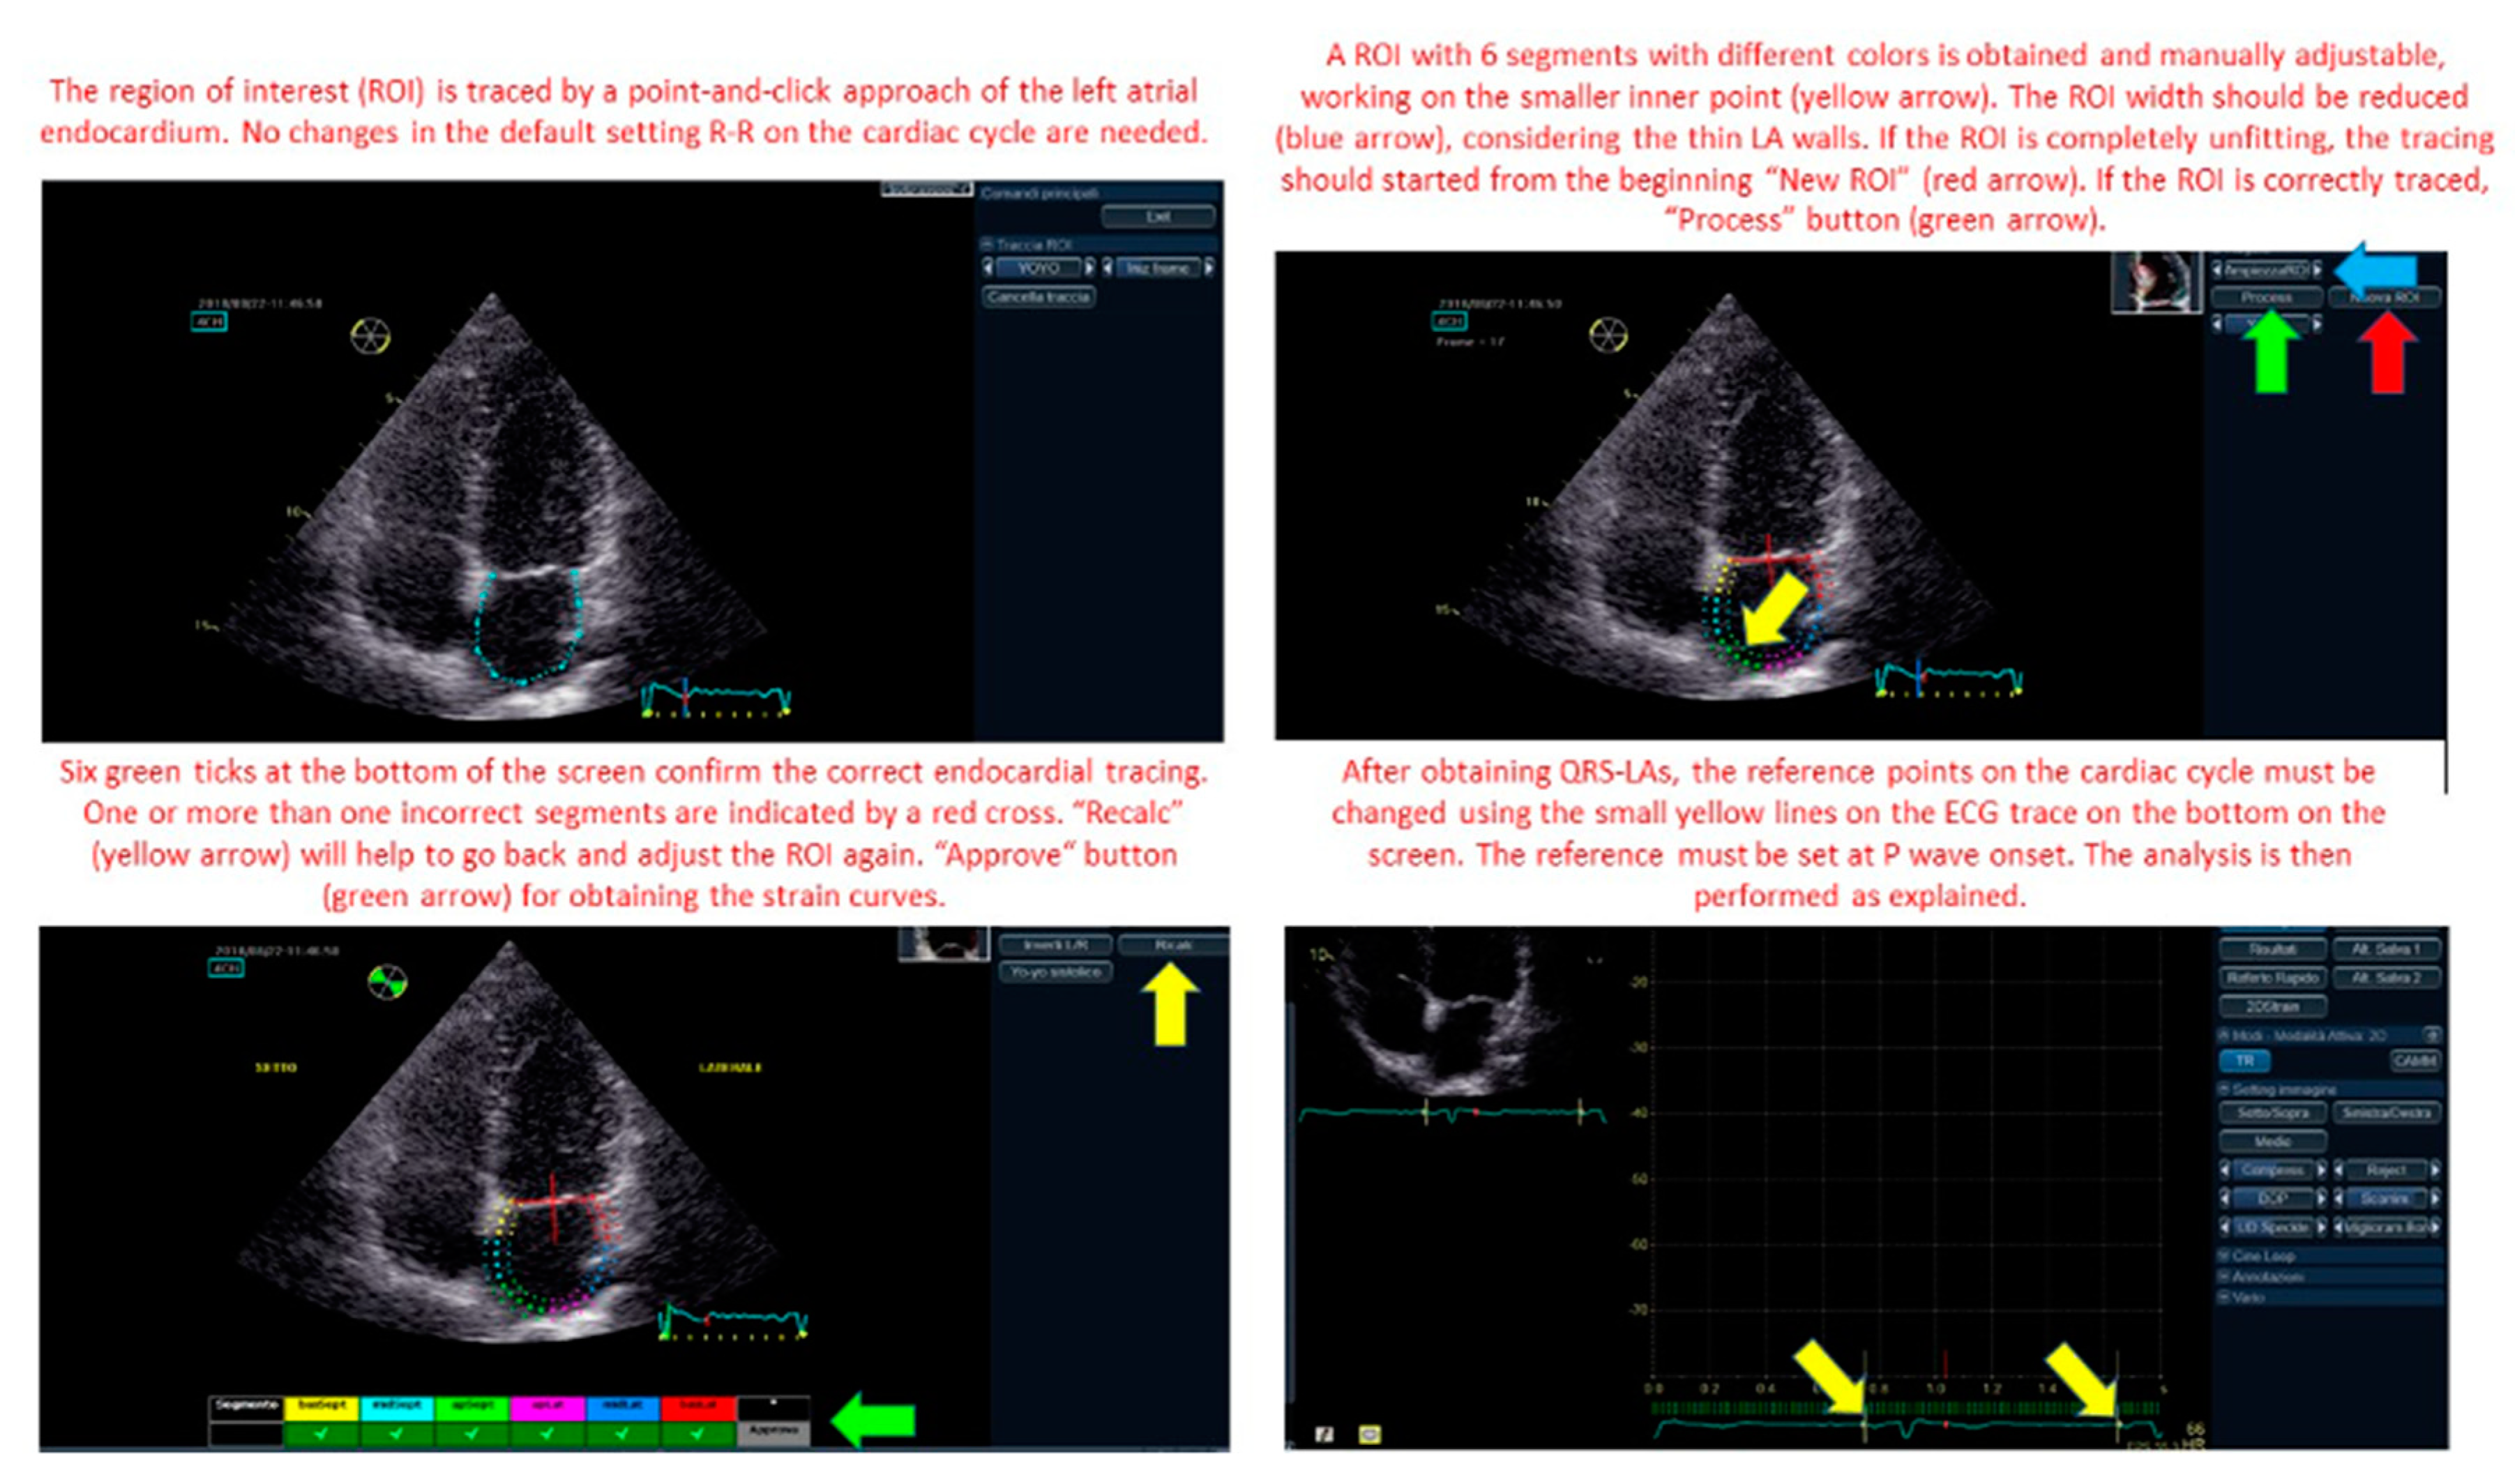

Each echocardiographer calculated LA parameters of longitudinal deformation with both techniques. For QRS method, LA endocardial border was manually traced at LV end-systole in both apical views. The software automatically generated a region of interest (ROI) including six segments with different colours per view. Then, the ROI was manually adjusted to include the thickness of the LA myocardium and optimize tracking quality analysis (Figure 1). A curve was then generated for each of the 12 atrial segments during the QRS-to-QRS cardiac cycle analysis. The ECG reference was then changed on the software to the P wave, leading to a P wave-to-P wave cardiac cycle analysis (Figure 1). The ROI was again traced and adjusted in both apical views and LA strain curves were generated.

Figure 1.

Left atrial (LA_ strain region of interest (ROI) tracing and modification. Zero reference point for LA strain analysis changing from QRS to P wave.

The figure shows and explain how to correctly trace the left atrial strain region of interest (ROI) and how to modify the zero reference for the analysis from the QRS to P wave.